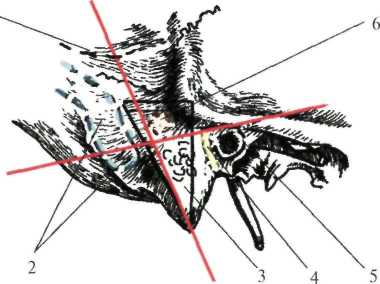

Анатомия сосцевидного отростка